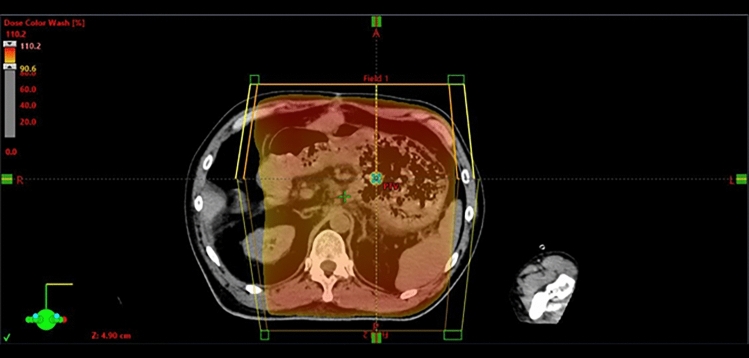

虽然有报道称止血放疗是治疗胃癌出血的有效方法,但其作用机制和即时效果尚不清楚。我们报告了一个胃癌出血的病例,这是由整个胃肿瘤和左侧胃动脉假性动脉瘤在肿瘤相关溃疡处引起的。患者因全胃肿瘤出血行放射治疗,随后经导管动脉栓塞治疗左胃动脉假性动脉瘤。放疗后2小时单段8 Gy x线造影显示,栓塞后的胃左动脉、未栓塞的胃右动脉、胃左动脉和肝左动脉总干的肿瘤血管和肿瘤染色均消失,推测未栓塞动脉的这些血管造影改变反映了止血放疗的即时效果。止血治疗后,患者生命体征稳定,血红蛋白水平未下降,提示立即止血。本病例提示止血机制与早期肿瘤血管改变有关,说明止血放疗可实现快速止血控制。因此,止血放疗应被视为胃癌出血的紧急治疗选择。

Although hemostatic radiotherapy has been reported as an effective treatment for gastric cancer bleeding, its mechanism and immediate effects remain unclear. We experienced a case of gastric cancer bleeding originating from both the whole gastric tumor and a left gastric arterial pseudoaneurysm at the tumor-associated ulcer. The patient was treated with radiotherapy for bleeding from the whole gastric tumor, followed by transcatheter arterial embolization for the left gastric arterial pseudoaneurysm. Angiography performed two hours after radiotherapy with an X-ray of 8 Gy in a single fraction revealed the disappearance of both tumor vessels and tumor stain from not only the embolized left gastric artery but also both the non-embolized right gastric artery and common trunk of the left gastric and the left hepatic arteries, which indicated these angiographic changes of the non-embolized arteries were presumed to reflect an immediate effect of hemostatic radiotherapy. Following hemostatic treatments, the patient's vital signs stabilized, and hemoglobin levels did not decrease, indicating immediate hemostasis. This case suggests a link between hemostatic mechanism and early tumor vessel changes, indicating that hemostatic radiotherapy can achieve rapid bleeding control. Therefore, hemostatic radiotherapy should be considered an emergency treatment option for gastric cancer bleeding.